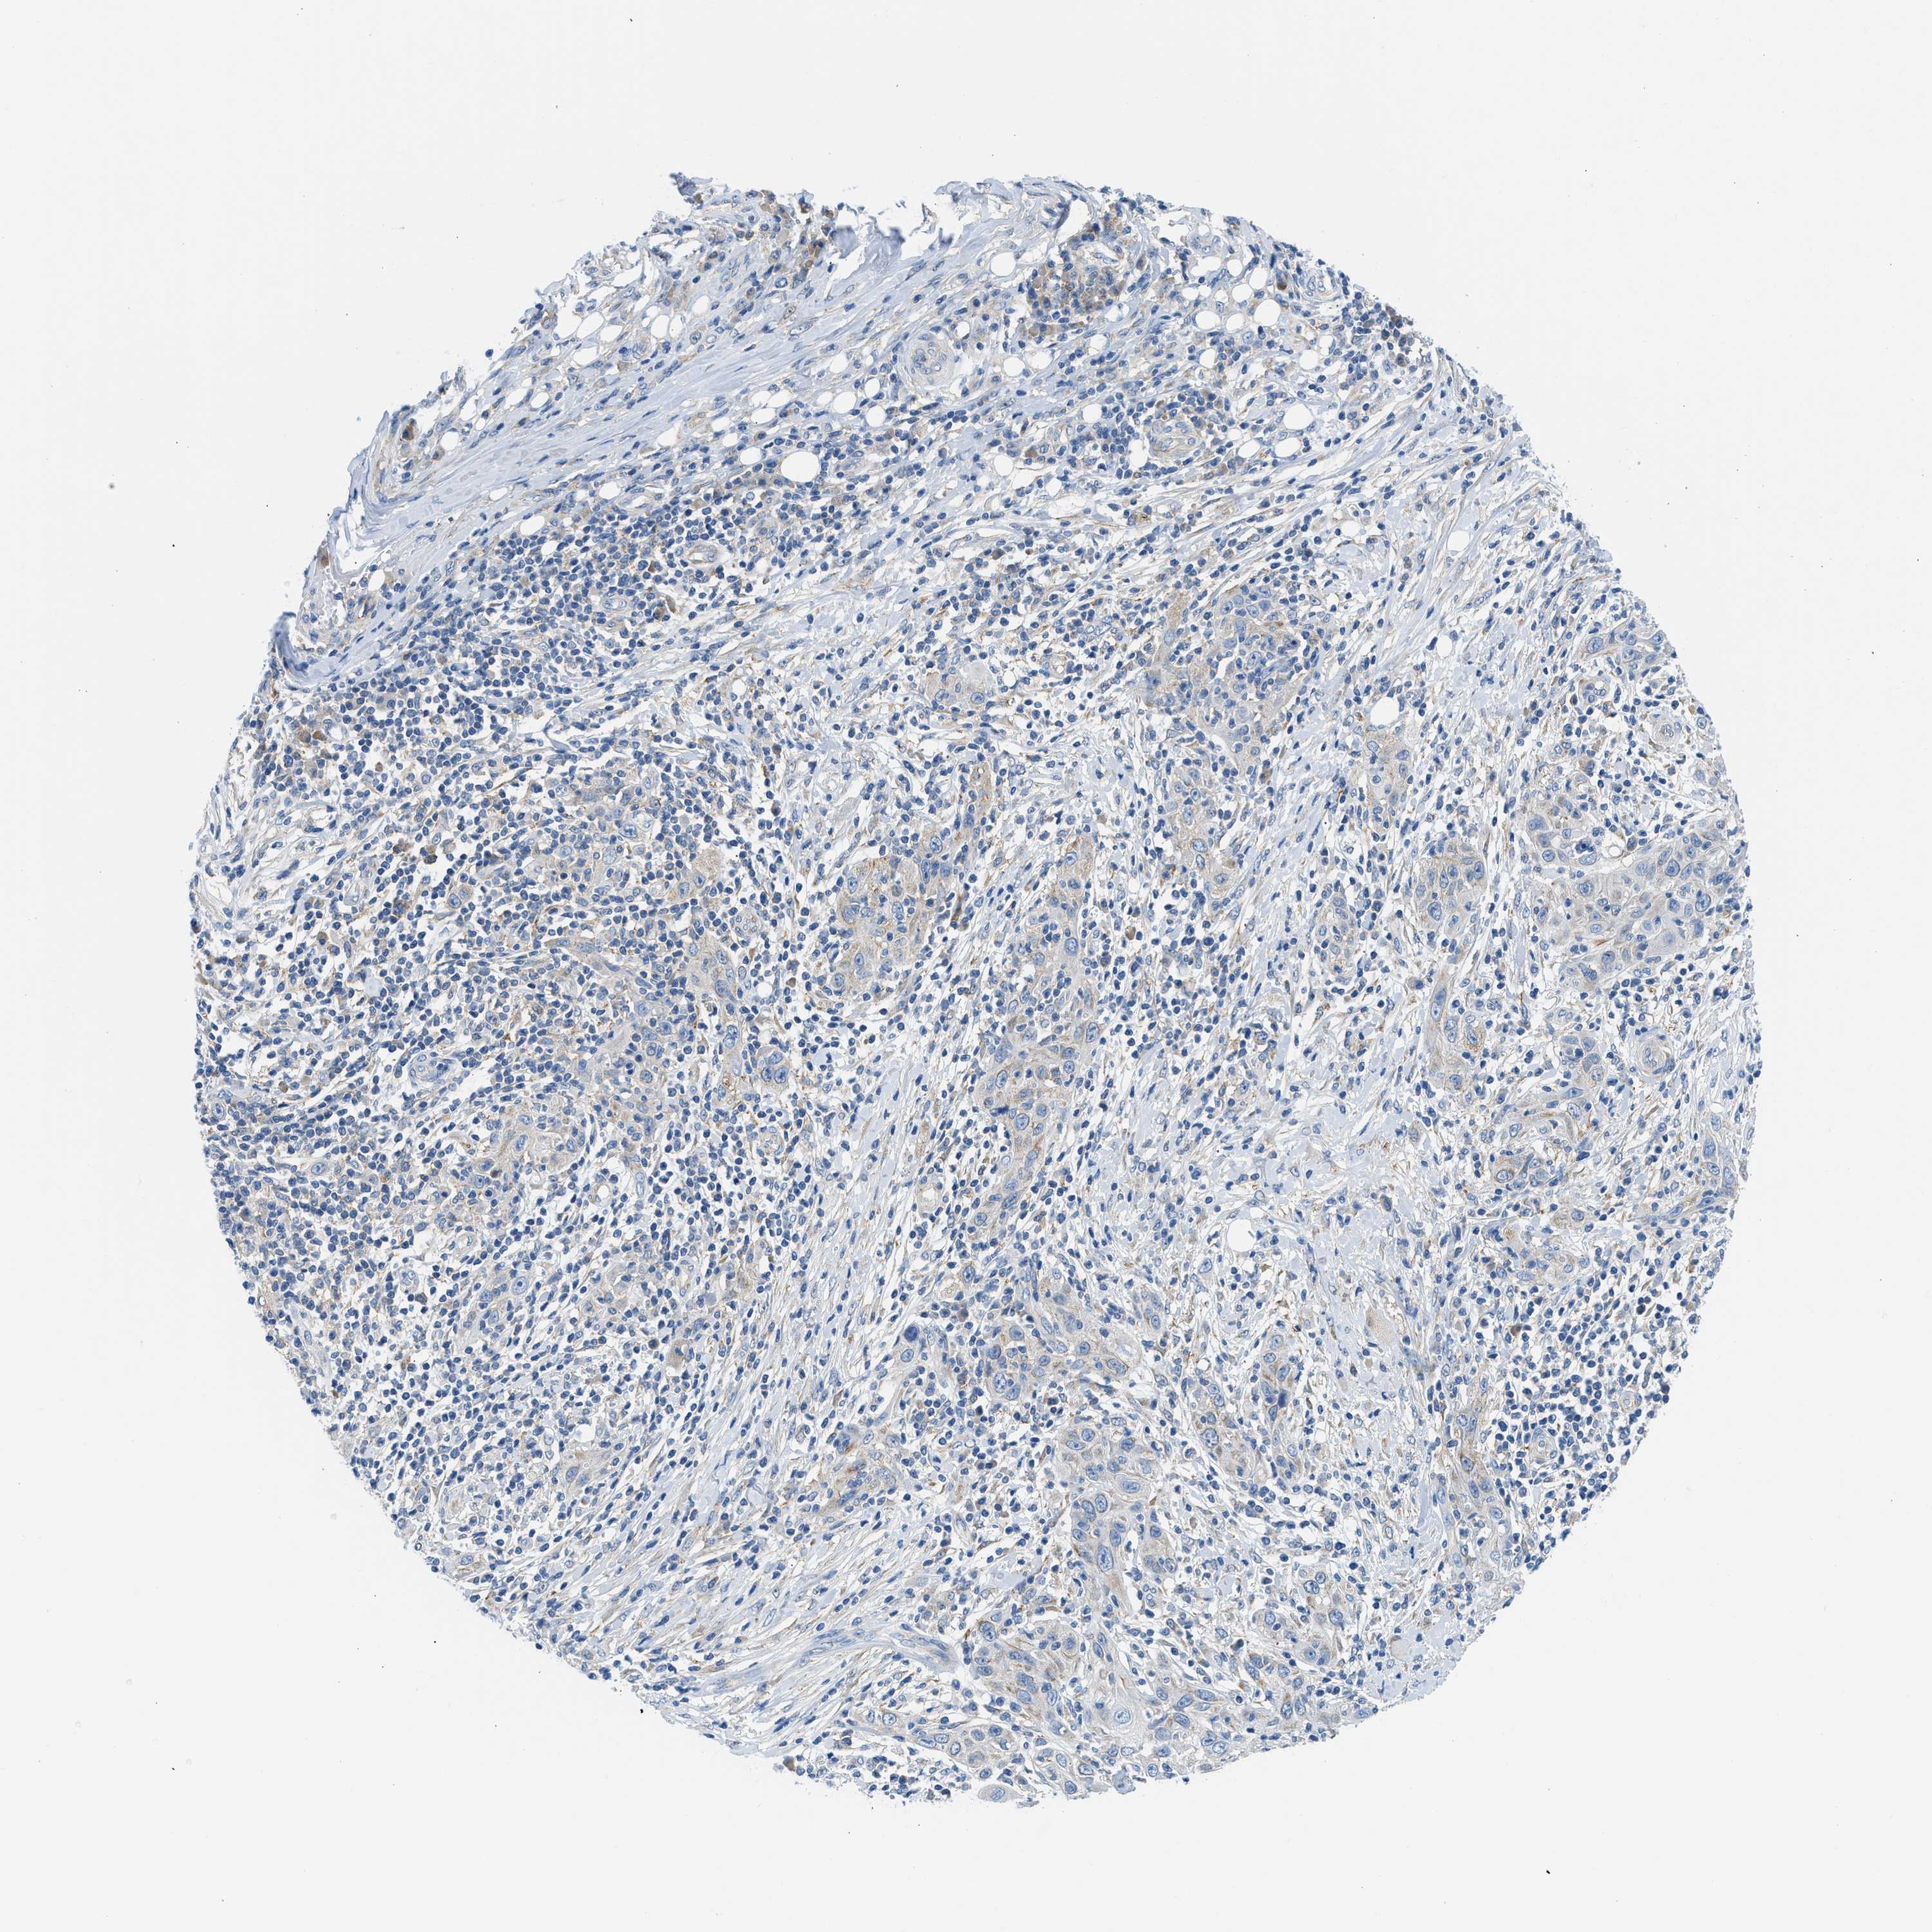

SKIN CANCER - Protein expressioni

A mouse-over function shows sample information and annotation data. Click on an image to view it in a full screen mode. Samples can be filtered based on level of antibody staining by selecting one or several of the following categories: high, medium, low and not detected. The assay and annotation is described here.

Antibody stainingi

Antibody staining in the annotated cell types in the current human tissue is reported as not detected, low, medium, or high, based on conventional immunohistochemistry profiling in selected tissues. This score is based on the combination of the staining intensity and fraction of stained cells.

Each image is clickable and will lead to virtual microscopy that enables deeper exploration of all samples and also displays staining intensity scores, fraction scores and subcellular localization as well as patient and tissue information for each sample.

Antibody HPA018525

Squamous cell carcinoma, NOS

Squamous cell carcinoma, metastatic, NOS

Basal cell carcinoma